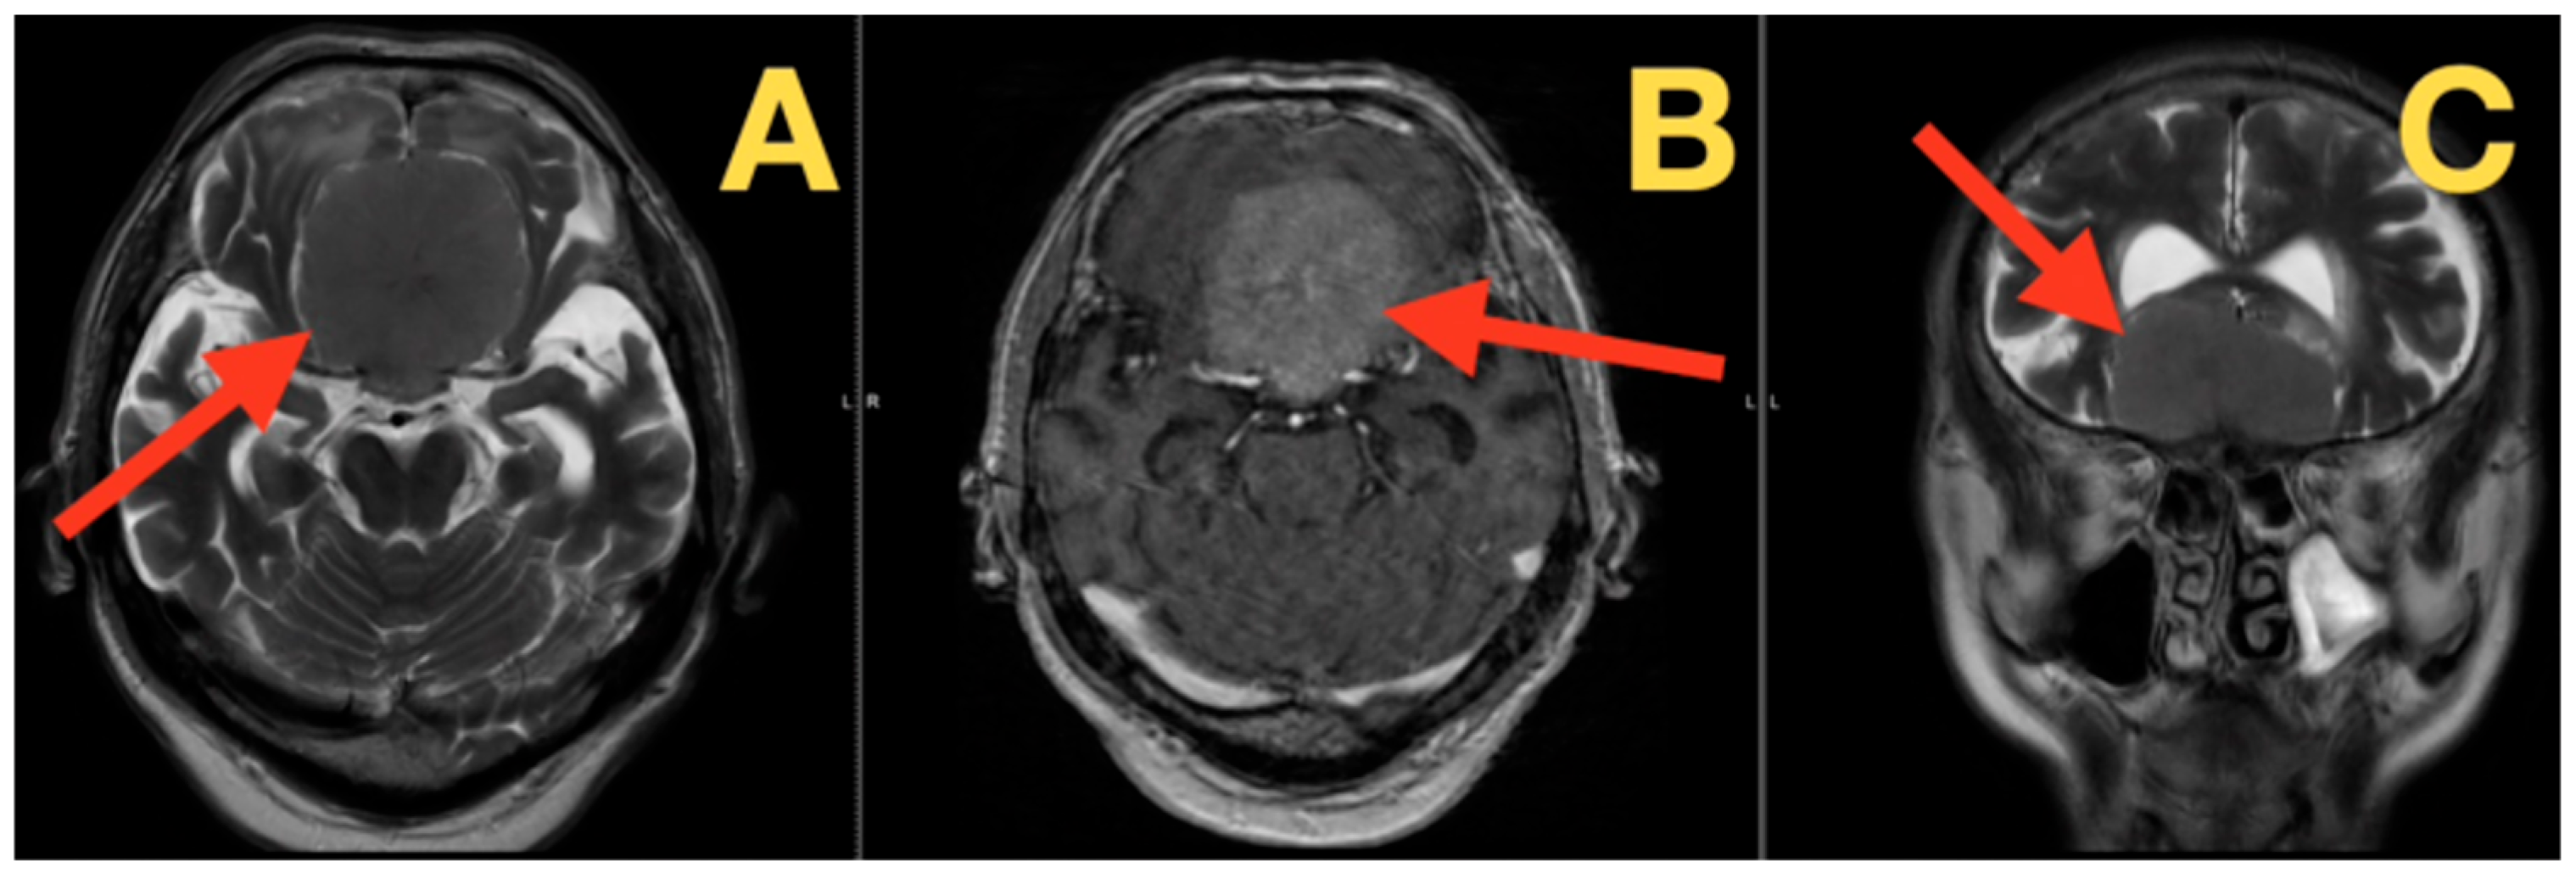

2.4. Preoperative Imaging and Quantitative Metrics